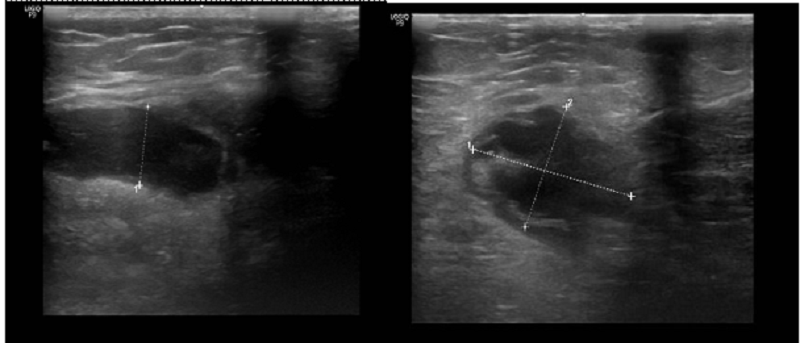

- Siêu âm: Khớp trái có hình ảnh tràn dịch khớp gối, thoái hóa khớp gối trái, kén bao hoạt khoeo chân trái.

Hình ảnh tràn dịch khớp gối trái ghi nhận trên siêu âm